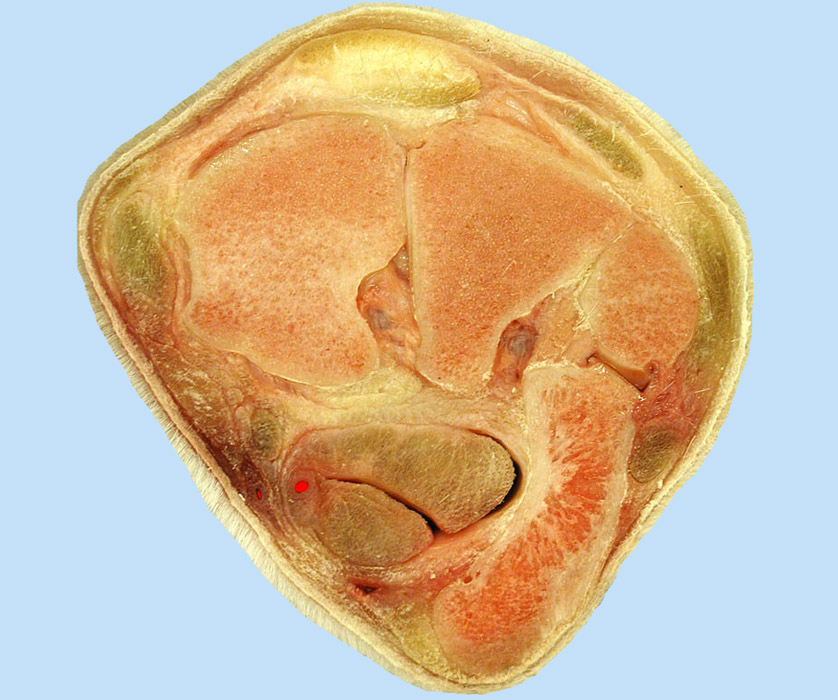

Carpal cross section, the carpal canal contains the digital flexor tendons (4, 5). This canal is formed by the accessory carpal bone (1) laterally, the flexor retinaculum (2) medially, and the palmar carpal ligament (3) dorsally. 4, superficial digital flexor tendon (SDFT); 5, deep digital flexor tendon (DDFT); 6, medial palmar a.; 7, radial a.; 8, radial carpal bone; 9, intermediate carpal bone; 10, ulnar carpal bone; 11, extensor carpi radialis tendon near insertion on Mc3; 12, medial collateral ligament.